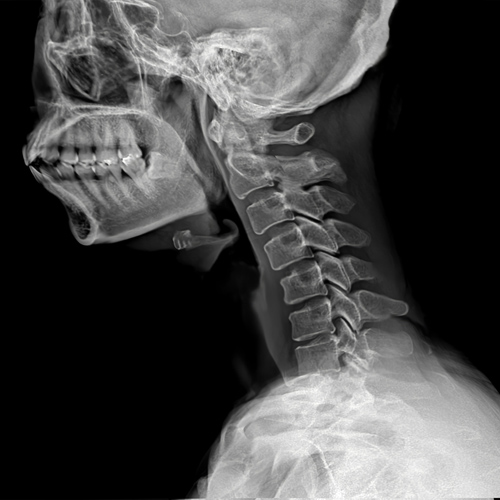

목디스크는 의사의 진찰 소견이 중요합니다.

단순 방사선 촬영은 목 디스크를 보다 강력하게 의심하는 방법은 되지만 확진은 어렵습니다.

근전도 검사가 의료 보험 적용이 되는 디스크 확진 방법이며, MRI는 영상으로 목 디스크가 뒤로 밀린 것을 확인할 수 있습니다.